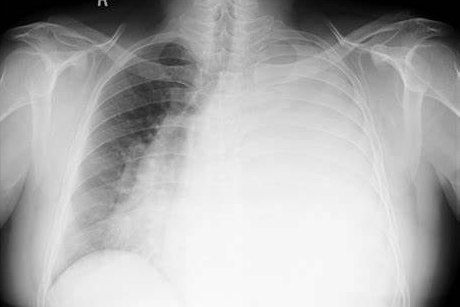

那为什么叫白肺呢?这是因为正常健康的肺,都是由通气功能正常的肺泡组成的,在X光和CT上都是透光的,并且显示为“黑色”。但如果肺部有严重的疾病(比如肺炎或者肺部肿瘤),或者有大量的胸腔积液,让健康的肺组织不再具有正常的通气和其他交换功能,肺泡组织被破坏了,这时候在X光和CT上就表现为“白色”。

一般情况下,我们说的白肺是指广泛的大面积的,至少累及到一个肺叶的病变,如果只是部分肺叶的改变,一般不称做白肺。

白肺